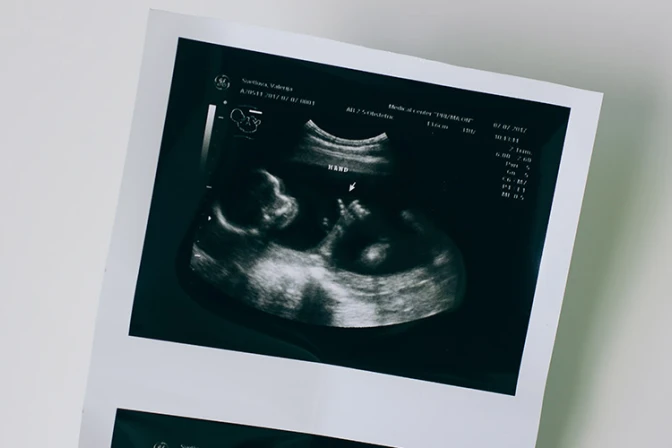

En Hungría entró en vigor una ley que exige que los médicos hagan que las madres que quieren abortar escuchen el sonido de los latidos del corazón de su bebé antes de cualquier procedimiento.

Con esta decisión, los médicos deben firmar un documento que verifique que las mujeres embarazadas recibieron "una indicación claramente identificable de los signos vitales del feto" antes de proceder con cualquier forma de aborto.

También señaló que los equipos modernos pueden detectar los latidos del corazón al principio del embarazo, lo que puede proporcionar "información más completa para las mujeres embarazadas".